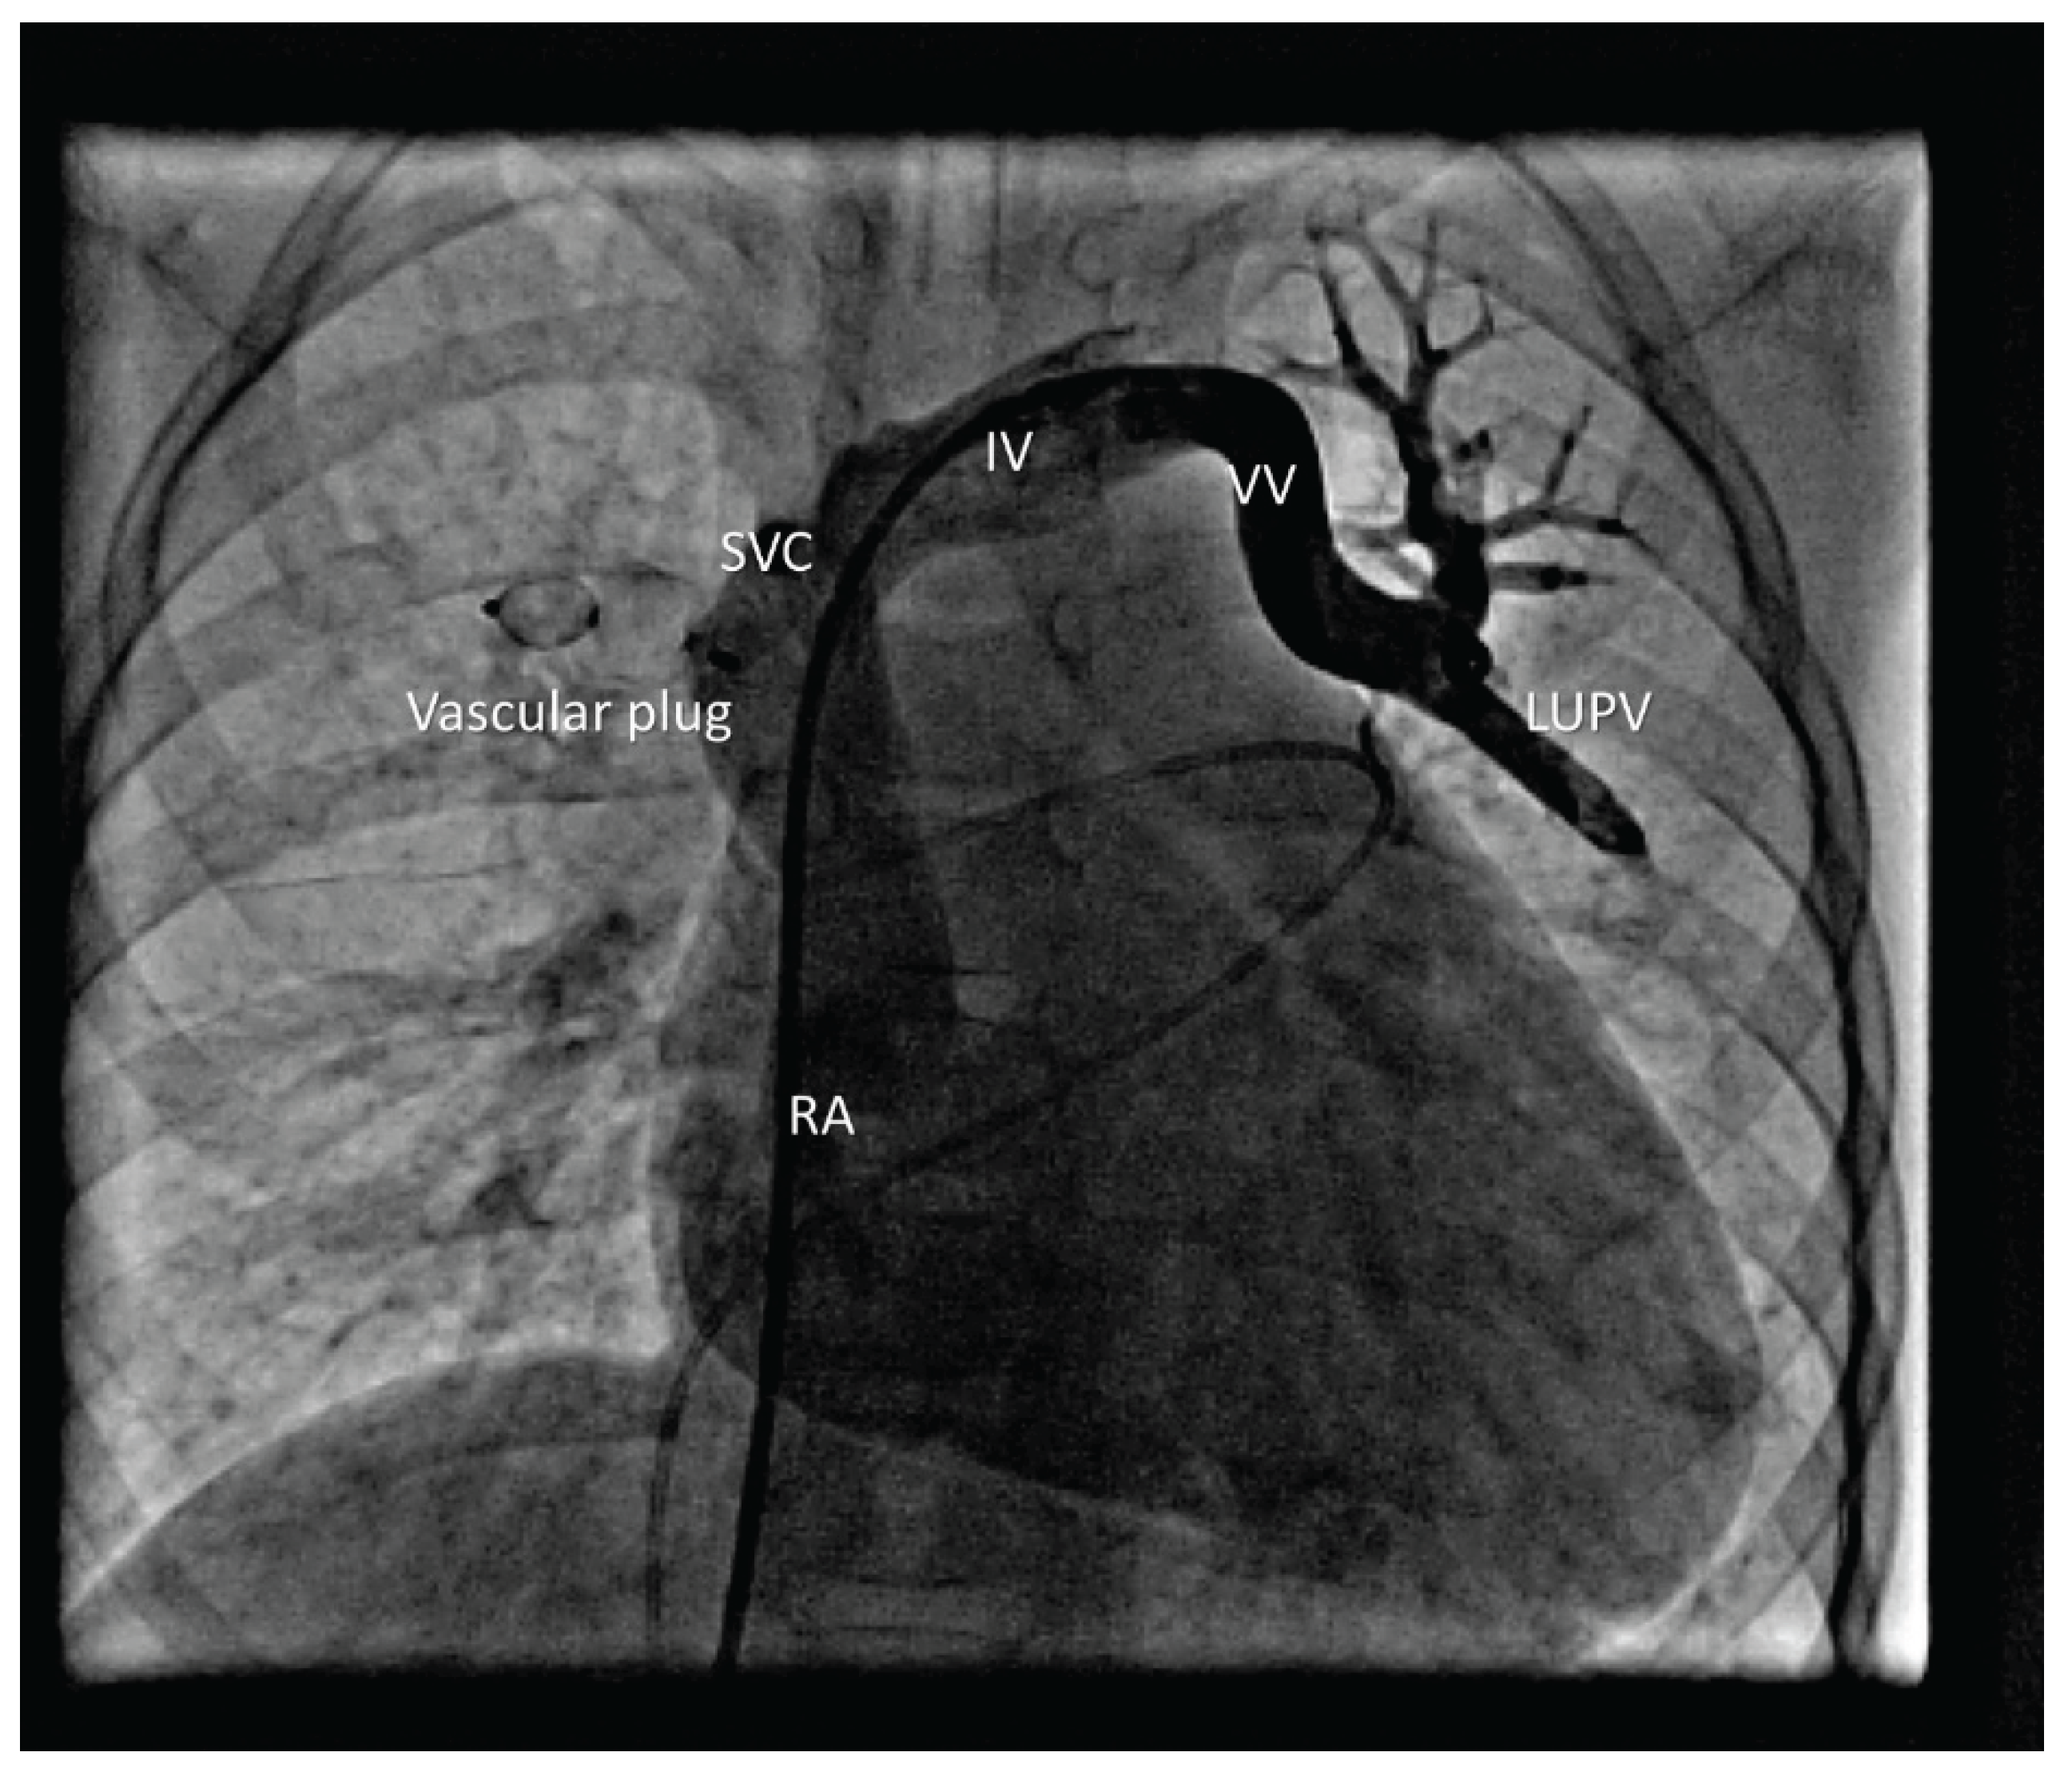

Device position was verified, and control angiography showed no venous congestion in the right upper lobe before release. A 7 Fr sheath was then placed in the left femoral vein, and a 7 Fr right guiding catheter was advanced into the VV. A 12 mm Amplatzer Vascular Plug I was delivered. After verifying correct position and excluding pulmonary venous congestion, the device was released (Figure 4).

Figure 4. Vascular plug in the LUPV.